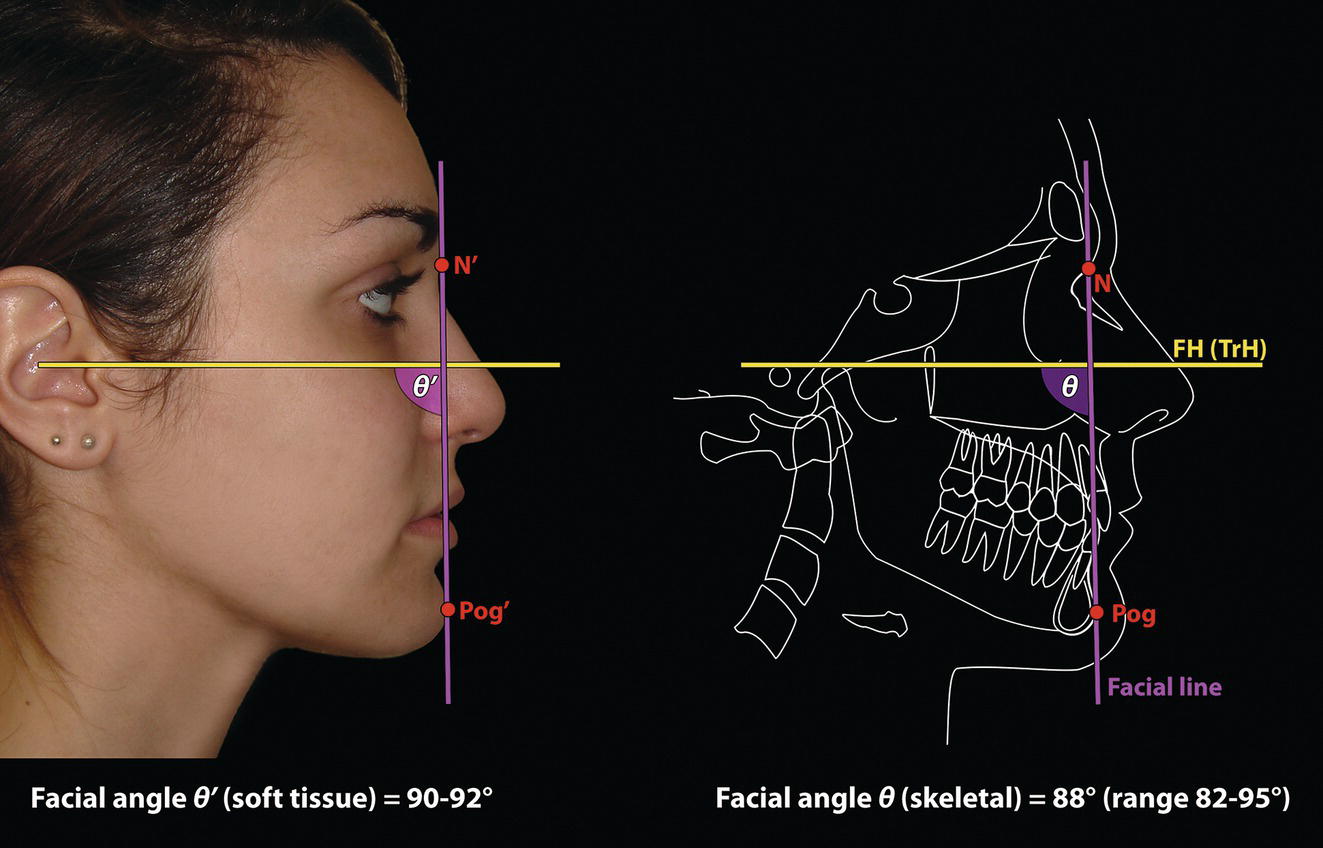

Facial angle (clinical/soft tissue) (Figure 8.12)

Facial angle (cephalometric/skeletal) (Figure 8.12)